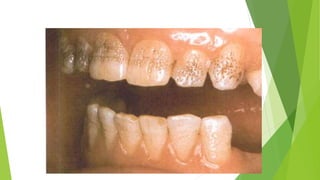

Amelogenesis

imperfecta,

hypocalcified type

The soft chalky enamel

was virtually of normal

thickness and form but

has chipped away during

mastication.